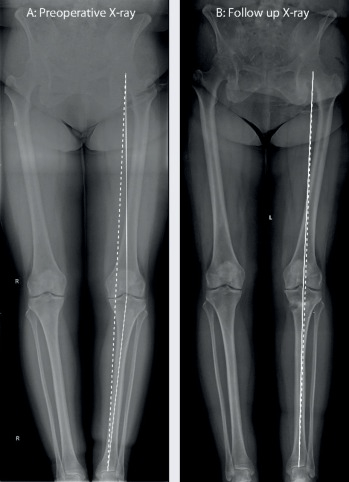

Lai noskaidrotu, vai šāda koriģējošā osteotomija būs pacientam piemērota, tiek veikti rentgenuzņēmumi, nosakot kāju varus/valgus leņķi, būtībā izsecinot, vai svars tiek vairāk nests uz ceļa iekšējās vai ārējās malas. Tiek uzskatīts, ka normāla kājas ass ir 5-7 grādi valgus pozīcijā, kad ceļgals ir nedaudz vērsts uz iekšu. Rentgens tiek veikts abām kājām visā to garumā, tajā tiek novilktas divas asis, mehāniskā un anatomiskā ass, kas norāda uz koriģējošo leņķi un ļauj pieņemt lēmumu kāda korekcija jāveic, lai pacients atgūtu anatomiski pareizu ceļa locītavas stāvokli.